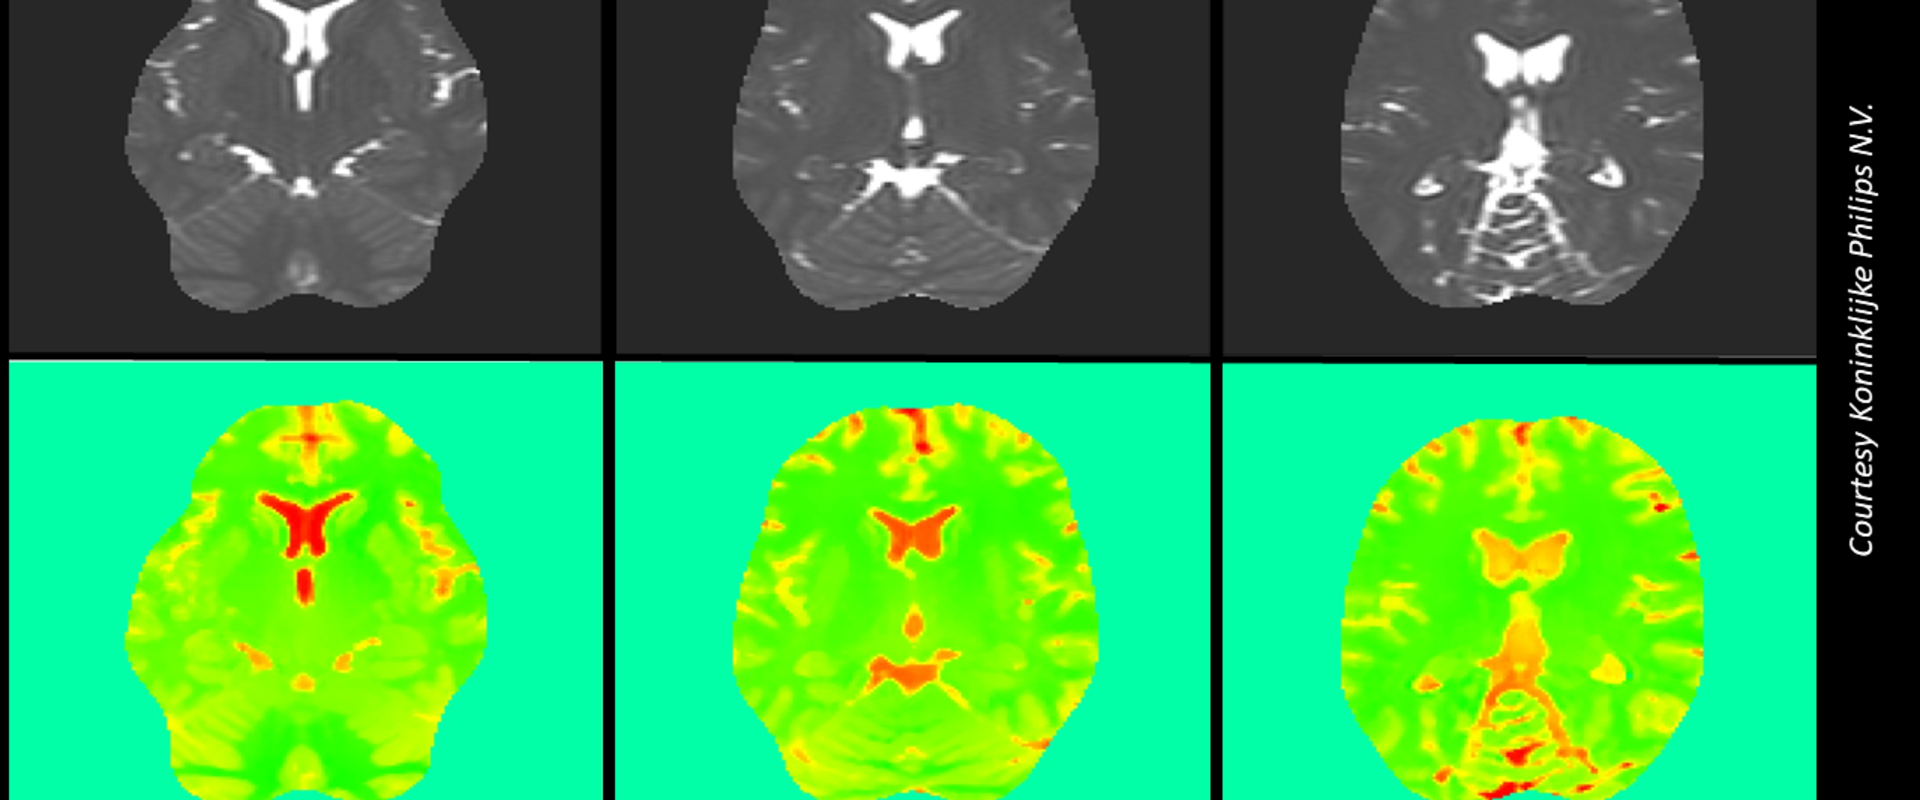

Electric Properties Tomography (EPT) is a MR-based method that does not require contrasting agents. Different body tissues have different electrical conductivities that interact with the scanners’ radiofrequency magnetic field, causing fluctuations that can be interpreted to provide quantitative data.

Measurement uncertainty was propagated through the mathematical model implemented in EPTlib, open-source software developed in the context of QUIERO, a project developing metrology for quantitative MRI. A major factor affecting the uncertainty propagation was the choice of kernel used, which defines the mathematical ‘smoothing’ applied to the voxels (the 3D representation of the pixels in scan images) during image processing.

The study revealed that the repeatability uncertainty was very small - indicating good repeatability for this technique. However, spatial fluctuations were observed in the obtained conductivity images, indicating the need of a more extended uncertainty assessment. To this end, a further set of scans of the phantom at different positions were performed in the QUIERO project to assess the MU associated with reproducibility. The resulting reproducibility uncertainty was in good agreement with the observed spatial fluctuations of each single scan.